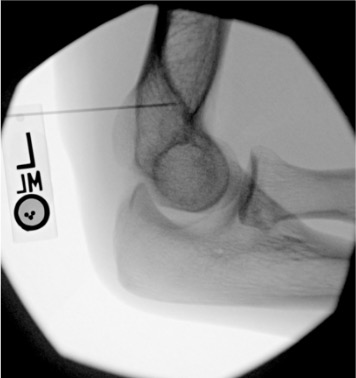

Elbow

Posterior (olecranon fossa)

Olecranon fossa with elbow flexed 90°; needle directed anteriorly into trochlear notch

8–10 mL

Intra-articular vs. extra-articular contrast distribution is the key fluoroscopic finding. Intra-articular: contrast flows freely along articular cartilage, fills joint recesses and capsular attachments. Extra-articular: contrast pools in soft tissue planes without joint recess filling — reposition needle before injecting diagnostic volume.